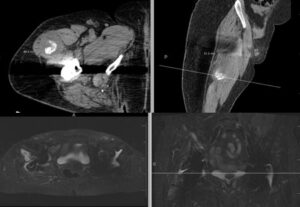

image_4_488